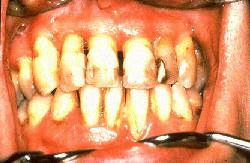

Mujer de 45 años de edad con la enfermedad periodontal severa antes del tratamiento. Los gingiva exhibe un color rojo intenso, hay bolsas profundas y sangrante al sondaje suave. El tratamiento consistió en gingivectomía, raspado y alisado radicular en los dientes superiores y solo raspado y alisado radicular en los inferiores. El incisivo lateral derecho superior y el central izquierdo inferior fueron extraídos por ser irrecuperables.